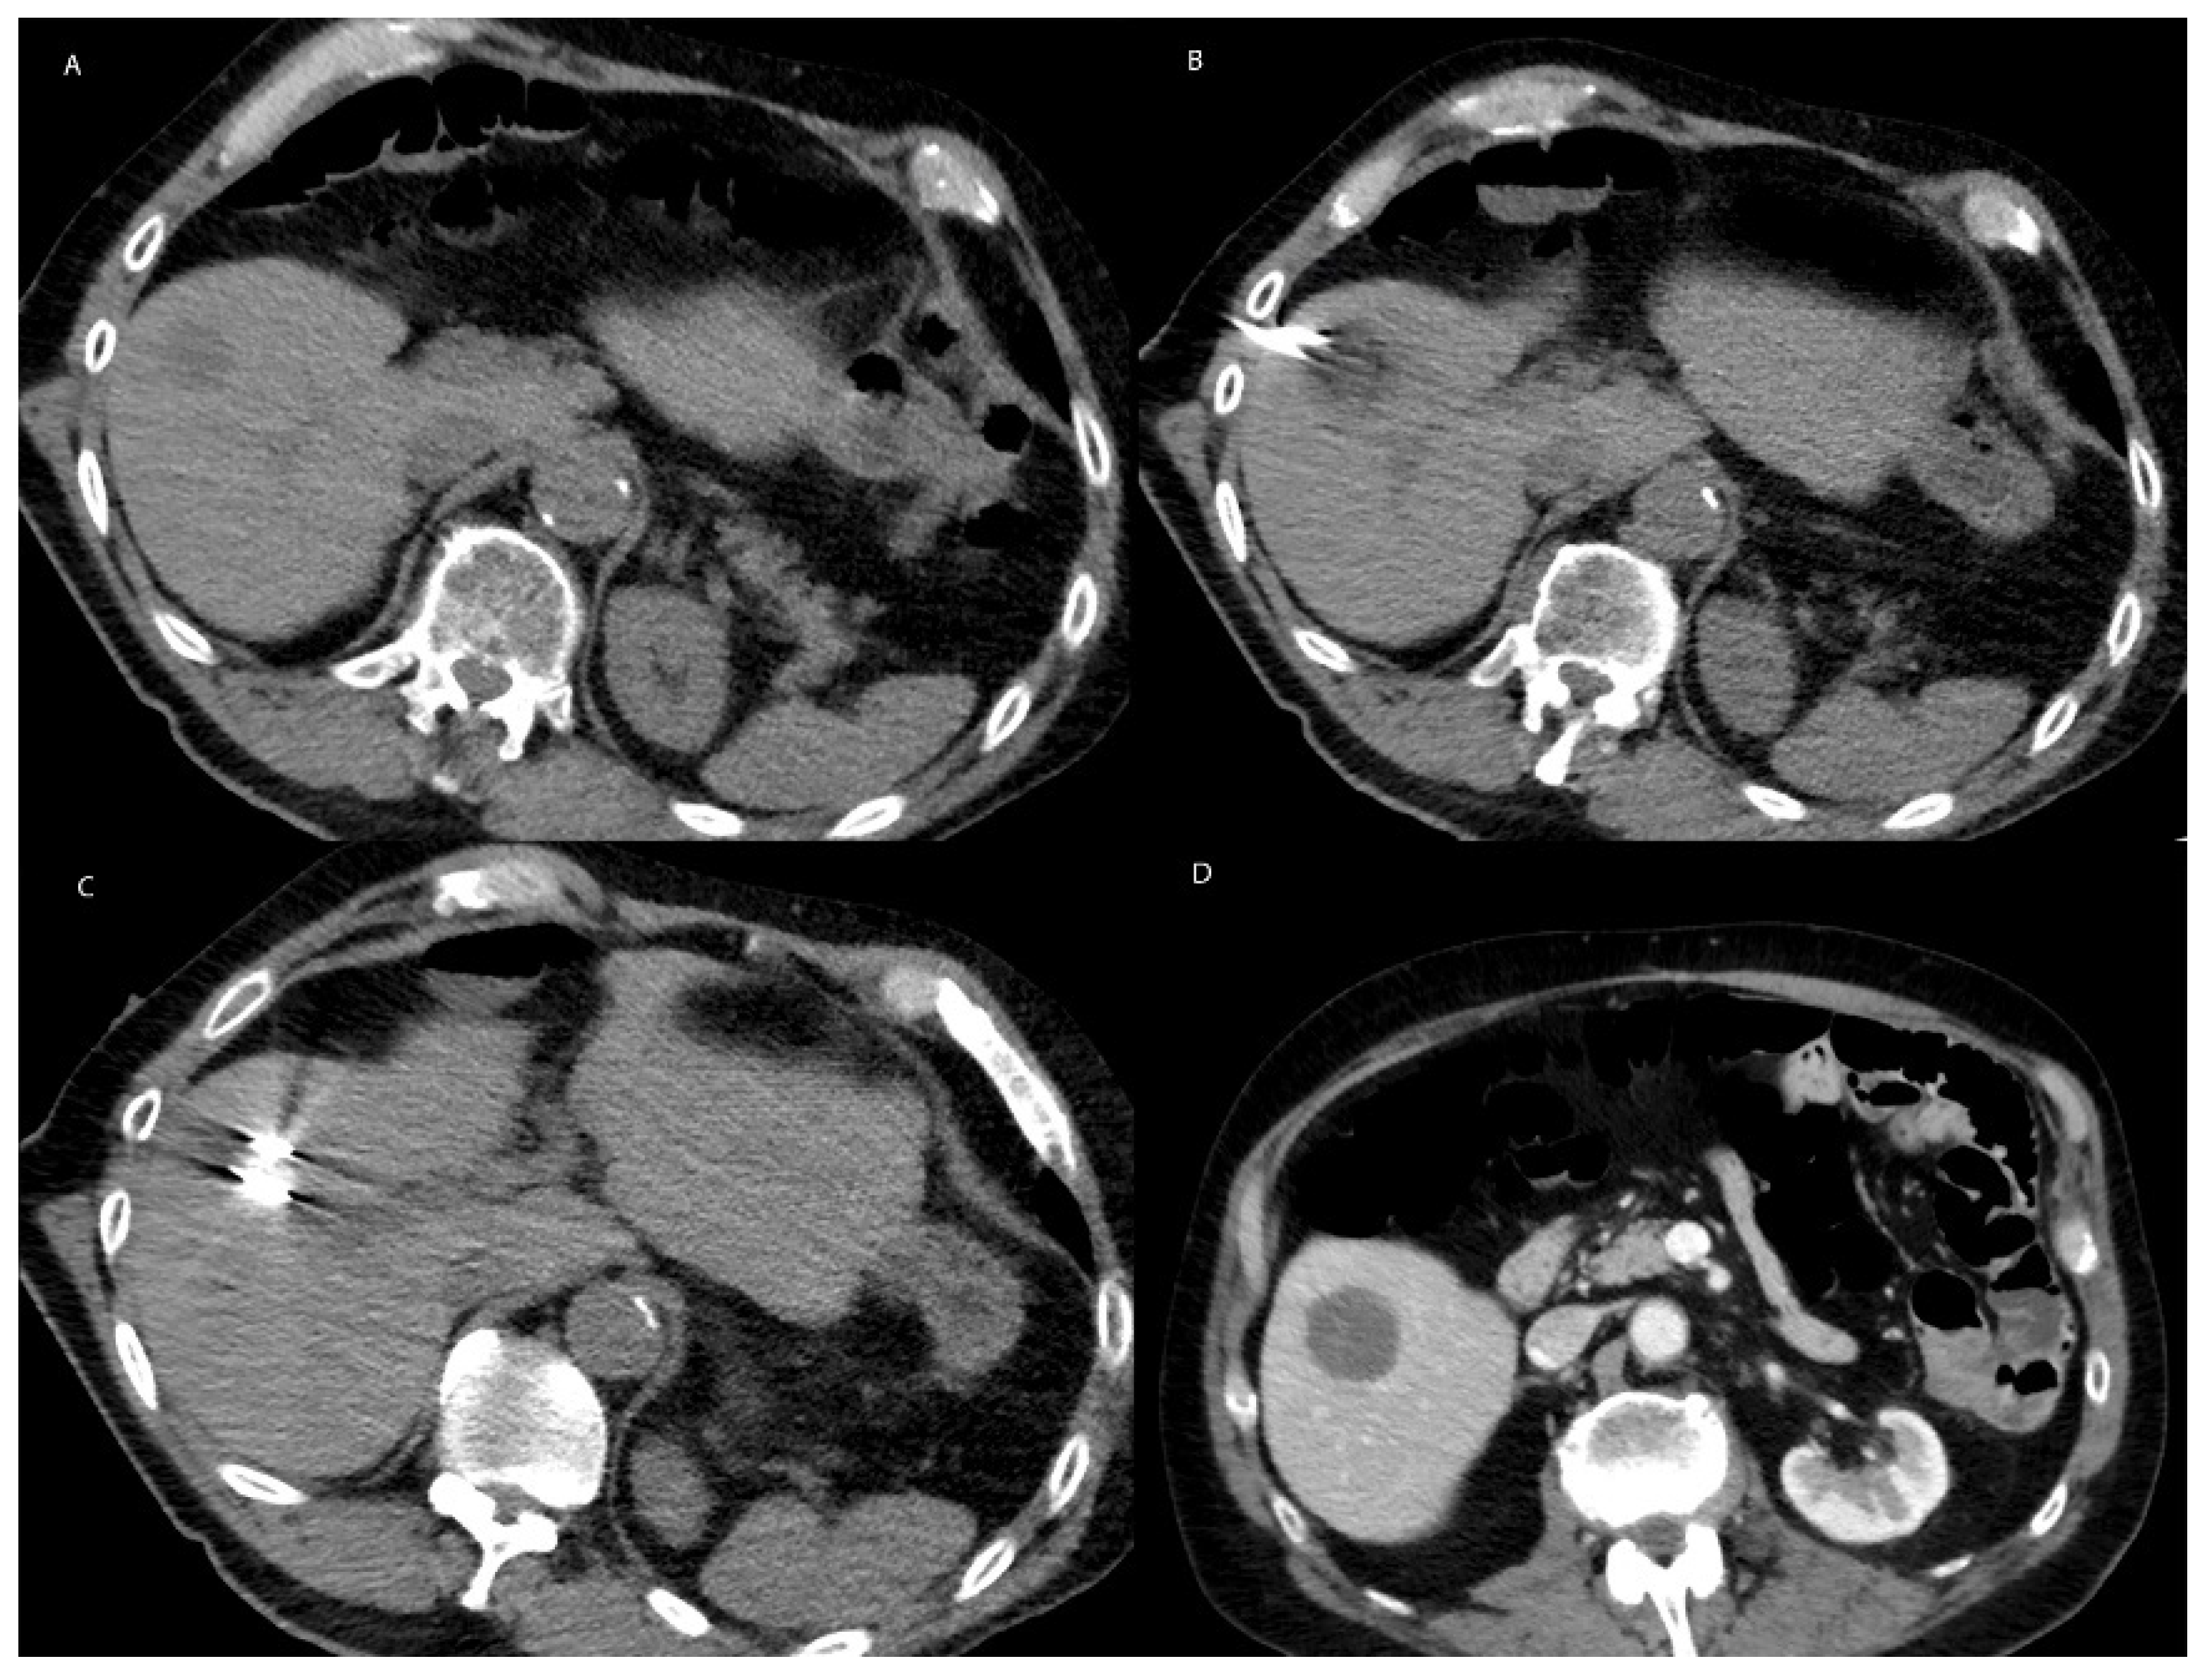

6.2. Microwave Ablation in Non-HCC Primary Liver Malignancy

6.3. Microwave Ablation in Metastatic Disease to the Liver